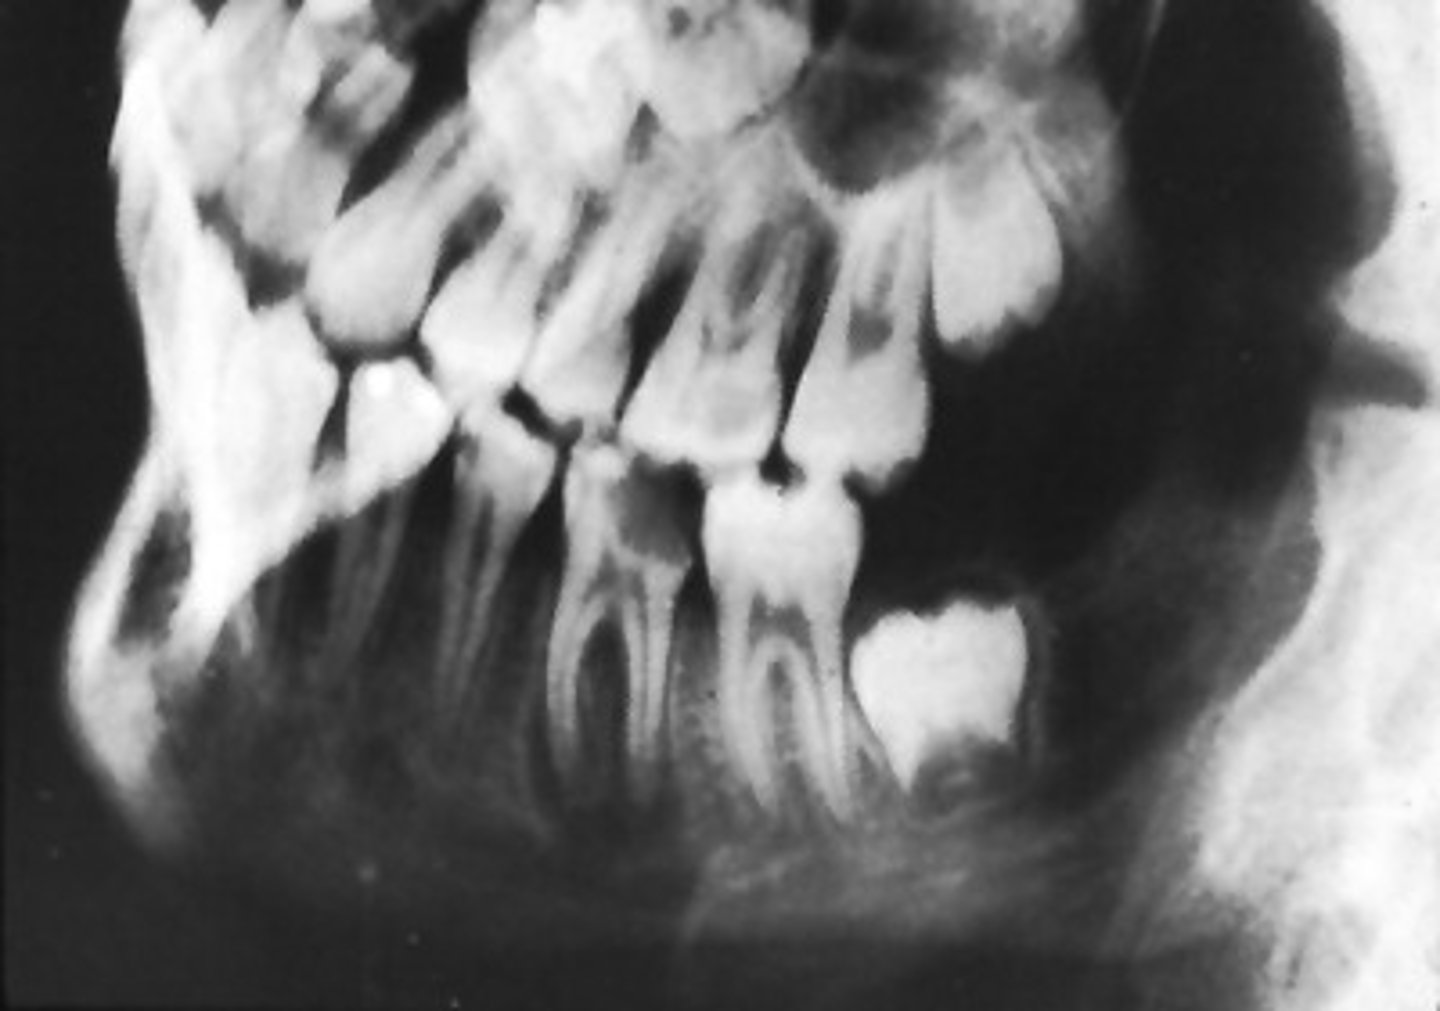

Most common diseases with supernumerary teeth?

Gardner's Syndrome, Cleidocranial Dysplasia

Cleidocranial Dysplasia characteristics?

Frontal bossing, missing clavicle